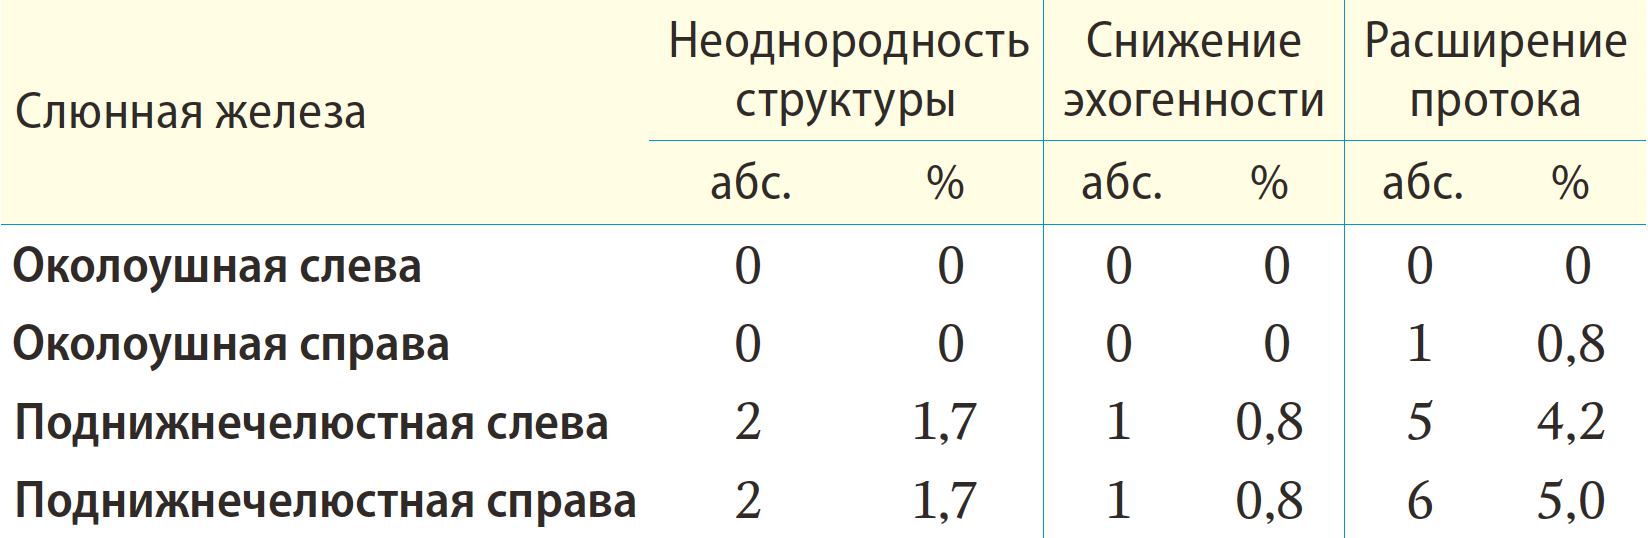

Результаты. Было выделено 3 эхографических признака состояния слюнных желез при сиаладените после радиойодтерапии: изменение эхогенности, расширение протоковой системы слюнных желез, неоднородность структуры. Изменение эхогенности наиболее часто происходит в левой околоушной слюнной железе (ОСЖ) — 6,7%. У пациентов с поражением ОСЖ справа и слева показатель расширения протока составлял 7,5 и 6,7% соответственно (расширение до 3 мм). Неоднородность структуры слюнных желез наиболее часто проявлялась в левой ОСЖ — 10%.

При сиаладените на фоне РЙТ происходят такие изменения паренхимы и протоковой системы слюнных паттернах картины УЗИ: появление неоднородности структуры железы, снижение эхогенности и расширение протоковой системы (табл. 1, 2).

У пациентов после радионуклидной терапии такие изменения имеются наиболее часто (6,7%) в левой ОСЖ. Неоднородность структуры железы может быть зарегистрирована у пациентов практически здоровых, без какихлибо клинических признаков поражения слюнных желез: в нашем исследовании в контрольной группе этот показатель составляет 0,83% в области каждой ПСЖ (см. табл. 2). Статистически достоверно значимой разницы между сторонами одних и тех же слюнных желез не выявлено у пациентов ни основной, ни контрольной группы (p=0,581 для ОСЖ, p=1,000 для ПСЖ). В основной группе изменение эхогенности было зарегистрировано одинаково часто и в ОСЖ, и в ПСЖ (p=0,123). В контрольной группе нарушение эхогенности без клинических признаков поражения СЖ чаще визуализировалось в ПСЖ (p=0,001). При сравнительном анализе частоты регистрации нарушения эхогенности между основной и контрольной группами, значимо чаще нарушение эхогенности выявлено у пациентов основной группы при анализе ОСЖ — p=0,004, при исследовании ПСЖ значимых различий не получено — p=0,312.

В контрольной группе этот показатель составляет в левой и правой ПСЖ по 4,2 и 5% соответственно, медиана расширения протока составила 0,5 мм [0,3—0,6] при максимальном расширении до 0,8 мм (рис. 2).

При сравнении степени расширения протоковой системы было отмечено более значительное расширение протоковой системы у пациентов после РЙТ в основной группе (p=0,003).

Неоднородность структуры

Неоднородность структуры является наиболее частым УЗ-паттерном, который можно обнаружить при УЗИ больших слюнных желез (p<0,001). У пациентов после радионуклидной терапии такие изменения чаще всего имеются в левой ОСЖ — 10%, в правой ОСЖ — 8%, в ПСЖ — 5%. В контрольной группе людей этот показатель не превышает 2% в области каждой ПСЖ. При сравнении частоты регистрации неоднородности структуры было выявлено значимо более частое наличие неоднородности в структуре ОСЖ после РЙТ (p<0,001), а в ПСЖ значимых различий не получено (p=0,151).